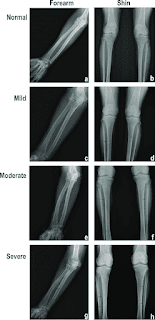

X-Ray of Forearm